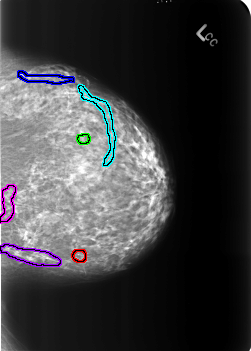

B_3239_1.LEFT_CC

FILE: B_3239_1.LEFT_CC.OVERLAY

TOTAL_ABNORMALITIES 6

ABNORMALITY 1

LESION_TYPE CALCIFICATION TYPE PUNCTATE DISTRIBUTION N/A

ASSESSMENT 2

SUBTLETY 4

PATHOLOGY BENIGN_WITHOUT_CALLBACK

TOTAL_OUTLINES 1

BOUNDARY

ABNORMALITY 2

ABNORMALITY 3

LESION_TYPE CALCIFICATION TYPE VASCULAR DISTRIBUTION N/A

ABNORMALITY 4

ABNORMALITY 5

ABNORMALITY 6